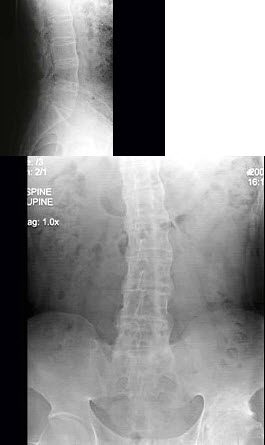

46、单项选择题

男,41岁,腰部酸肿不适10多年,近年加重,腰部活动受限,晨僵1年,腰椎正侧位片如图,最可能的诊断是()

A.腰椎退行性变

B.弥漫性骨质增生症

C.强直性脊椎炎

D.斯梯尔综合征

E.以上均不正确